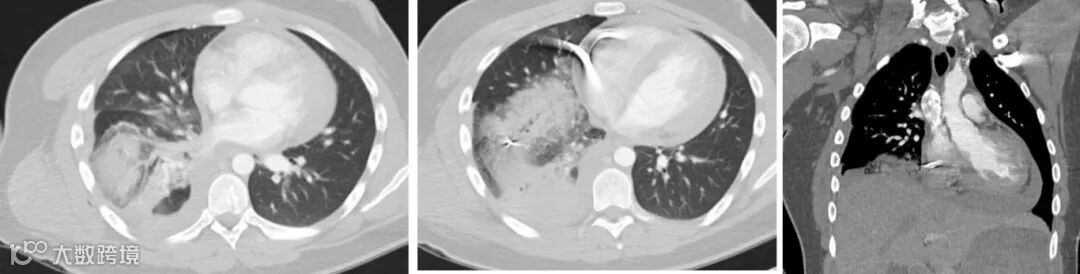

年轻男性,右侧胸部枪击伤。CT示右胸腔内金属弹片,右肺条带状线性实变影,病变与子弹轨迹吻合,与肺部撕裂和出血相符。右胸壁可见皮下气肿。

男,25岁,右胸枪击伤,右肺挫裂伤,右侧血气胸,弹片损失心包,出现心包积血。

男,30岁,右胸壁枪伤。CT扫描结果显示子弹进入椎管。子弹的轨迹导致右侧肋骨骨折,并导致肺出血和血气胸。